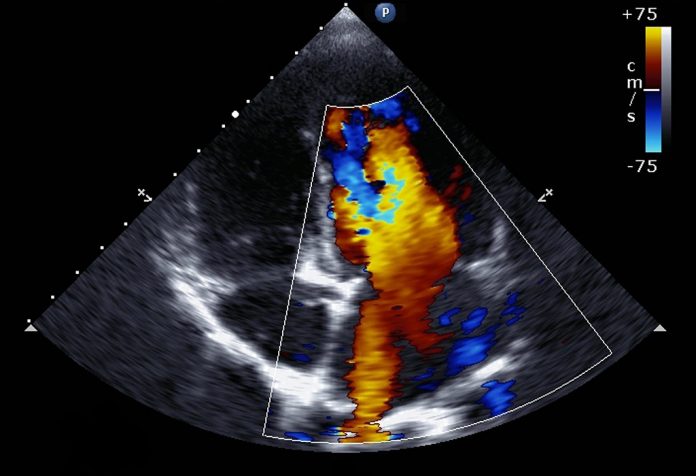

अल्ट्रासाउण्ड जस्तै प्रविधिबाट गर्भवती महिलाको पेटभित्रको बच्चाको मुटु परीक्षण गर्ने प्रविधिलाई फिटल इकोकार्डियोग्राफी भनिन्छ । यसले गर्भवती महिलाको गर्भमा हुर्किरहेको भ्रुणको मुटुलाई प्रष्ट देखाउँछ । मुटु स्वास्थ्य, यसको विकासको परीक्षण गर्ने यो प्रविधिले भ्रुणको मुटुको संरचना र कार्यक्षमतालाई विस्तृत रुपमा अवलोकन गर्न मद्दत गर्छ । मुटुमा कुनै प्रकारका चालसम्बन्धी गडबडीलाई पनि पहिचान गर्न यस प्रविधिले मद्दत गर्न सक्छ । गर्भभित्रको बच्चाको मुटुको समस्यालाई समयमै पहिचान गर्न, उचित उपचारमा सहयोग पुर्याउनुका साथै पछि आउन सक्ने जोखिमको पूर्वतयारी गर्न पनि सहयोग पुर्याउँछ ।

भ्रूण इकोकार्डियोग्राफी सामान्य स्क्यान जस्तै गरी गरिन्छ, जसमा गर्भवती महिलालाई खाना खाएर आउन सल्लाह दिइन्छ । यो प्रक्रिया गर्दा ४० देखि ४५ मिनेट लाग्छ । गर्भमा रहेको बच्चाको अवस्थाअनुसार यसले कम वा बढी समय लिन सक्छ । भ्रूण इकोकार्डियोग्राफी अनुभवी चिकित्सकबाट मात्र गराइन्छ ।

कार्डियाक इन्टर्भेन्सनमार्फत शरीरमा सफा अक्सिनयुक्त रगत जाने कडा भएका भल्बलाई बेलुनको सहायताले खोलिदिन्छ ।

साथै, अत्यन्त जटिल किसिमका मुटुरोग जसमा मुटुको माथिल्लो कोठाको भित्तामा प्वाल बनाएर ठूलो बनाइन्छ ।